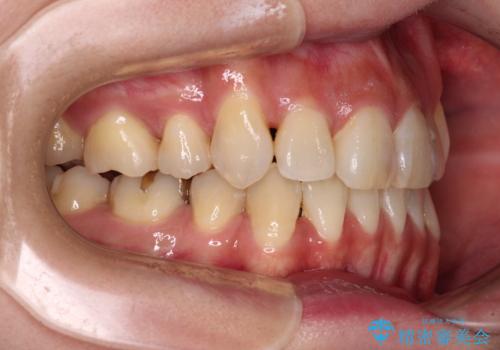

ハーフリンガルでの矯正治療は、表側矯正よりも期間がかかることが多く、抜歯矯正では3年以上かかることも珍しくありません。

デコボコが強い一方で出っ歯ではなかったため、抜歯したスペースを容易に閉じることができ、短期間での治療となりました。